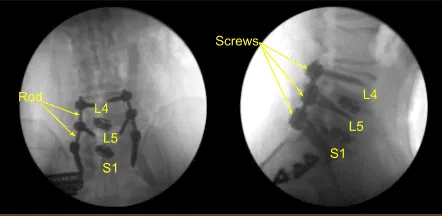

Precut-precontoured titanium rods were selected, contoured further and placed across the tulips from L4 to S1 bilaterally and secured with locking caps which were all final tightened with a torque and anti torque device. AP and lateral fluoroscopy was used to confirm appropriate sizing and positioning of the rods.

Additional CT scans were performed showing correct positioning of all the pedicle screw hardware. Neuromonitoring signals were stable. Next, we decorticated bilateral transverse processes and facet joints including sacral ala from L4 to S1 bilaterally with electric high-speed drill for the arthrodesis. The wound was irrigated copiously.